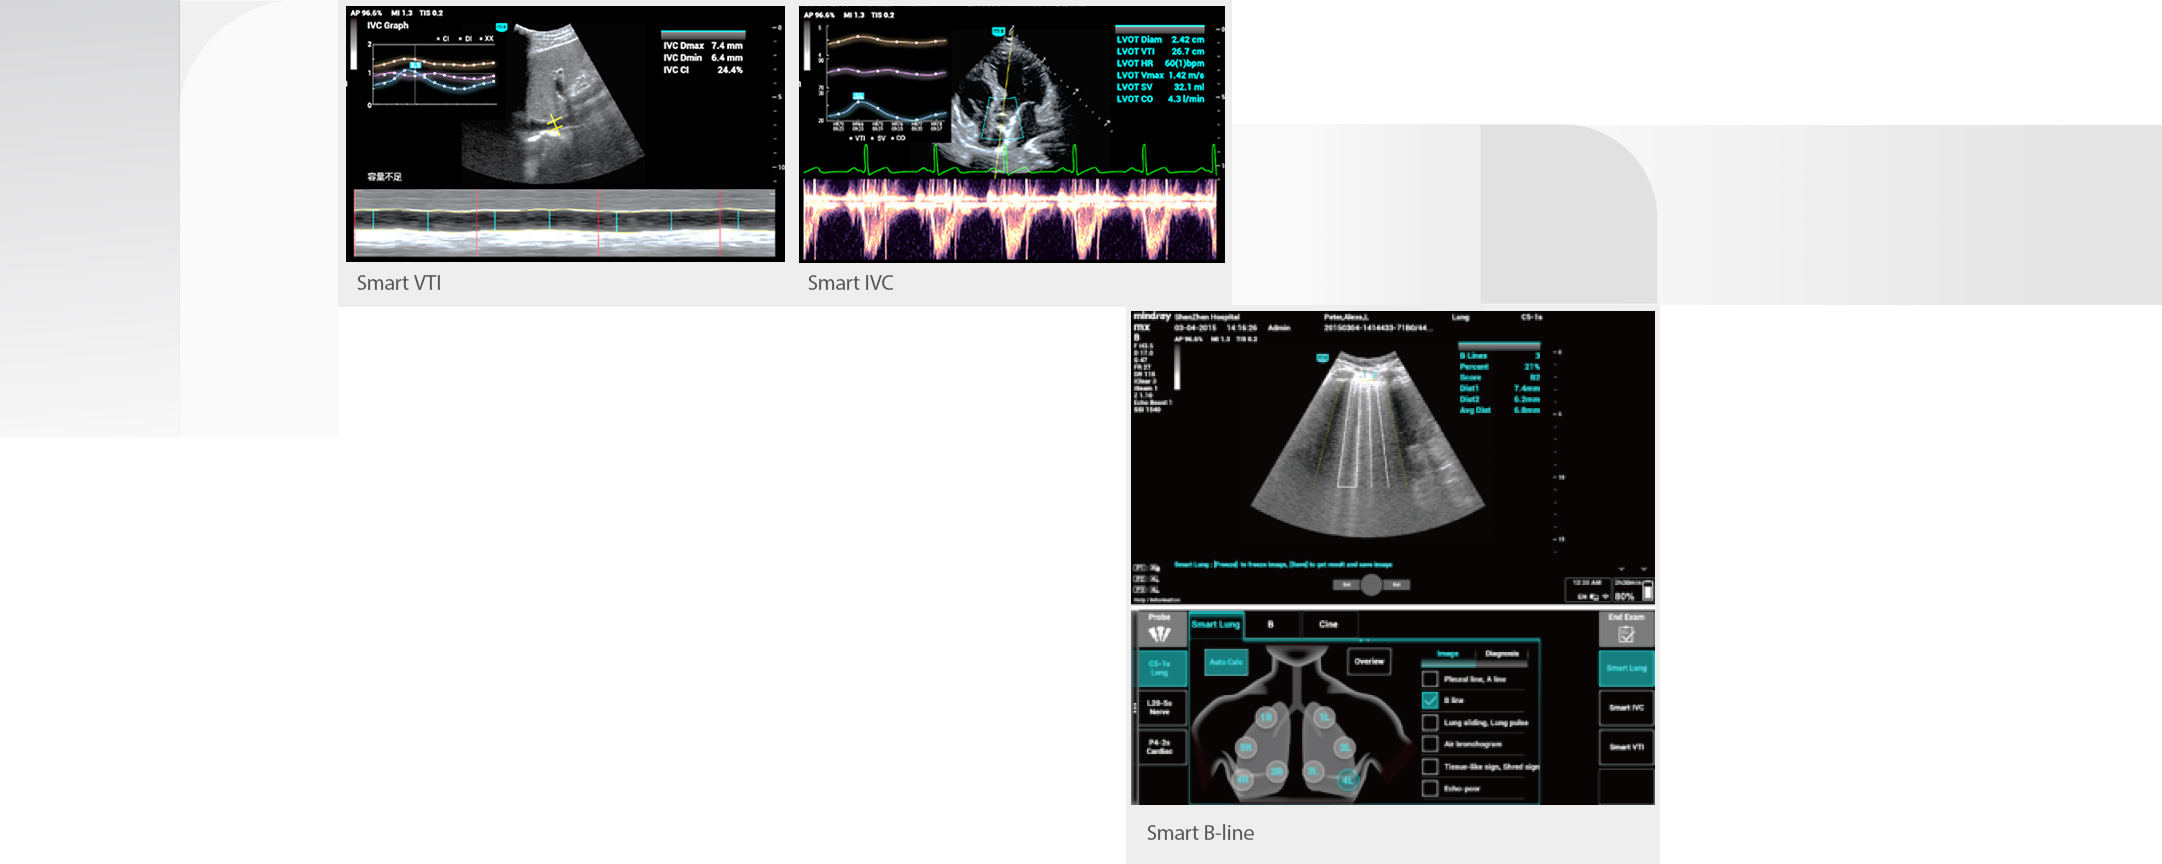

Yo?un bak?m ĂŒnitesindeki hastalarda ?o?unlukla kardiyopulmoner, hepatik ve renal organ yetmezli?i veya yetersizli?i vard?r, hayati belirtiler her an de?i?ebilir ve kritik hastalar?n yakla??k %90'?nda vĂŒcut s?v?lar? h?zla de?i?ir. Yo?un bak?m ĂŒnitesinde vĂŒcut s?v?lar?ndaki de?i?ikliklere yans?yan, yayg?n g?rĂŒlen anormallikler, gastrointestinal kanama, ciddi endokrin ve metabolik bozukluklar, su-elektrolit ve asit-baz dengesindeki bozukluklar, karaci?er ve b?brek fonksiyon bozuklu?udur.

Bu nedenle, hastalarda yak?n s?v? izlemesi ve do?ru hacim y?netimi yap?lmas? bĂŒyĂŒk ?nem ta??r. Ancak ultrason, hastalar?n kardiyopulmoner fonksiyonlar?n?n ve hemodinamiklerinin dinamik olarak de?erlendirilmesinde daha sezgisel olma avantaj?na sahiptir ve yo?un bak?m ĂŒnitesindeki sa?l?k mesle?i mensuplar?n?n, zaman?nda tedavi kararlar? almas?na ve tedavinin etkilerini ger?ek zamanl? olarak g?zlemlemesine yard?mc? olabilir.

Bu nedenle, hastalarda yak?n s?v? izlemesi ve do?ru hacim y?netimi yap?lmas? bĂŒyĂŒk ?nem ta??r. Ancak ultrason, hastalar?n kardiyopulmoner fonksiyonlar?n?n ve hemodinamiklerinin dinamik olarak de?erlendirilmesinde daha sezgisel olma avantaj?na sahiptir ve yo?un bak?m ĂŒnitesindeki sa?l?k mesle?i mensuplar?n?n, zaman?nda tedavi kararlar? almas?na ve tedavinin etkilerini ger?ek zamanl? olarak g?zlemlemesine yard?mc? olabilir.